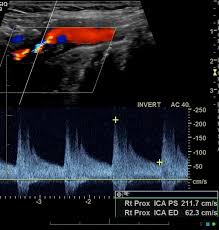

경동맥의 협착 정도와 혈류 속도를 확인해 향후 뇌졸중 발생 가능성을 예측할 수 있습니다.

혈관 내막 두께, 협착 정도, 혈류 속도 등을 확인할 수 있으며, 결과에 따라 추가 정밀검사가 필요할 수 있습니다.